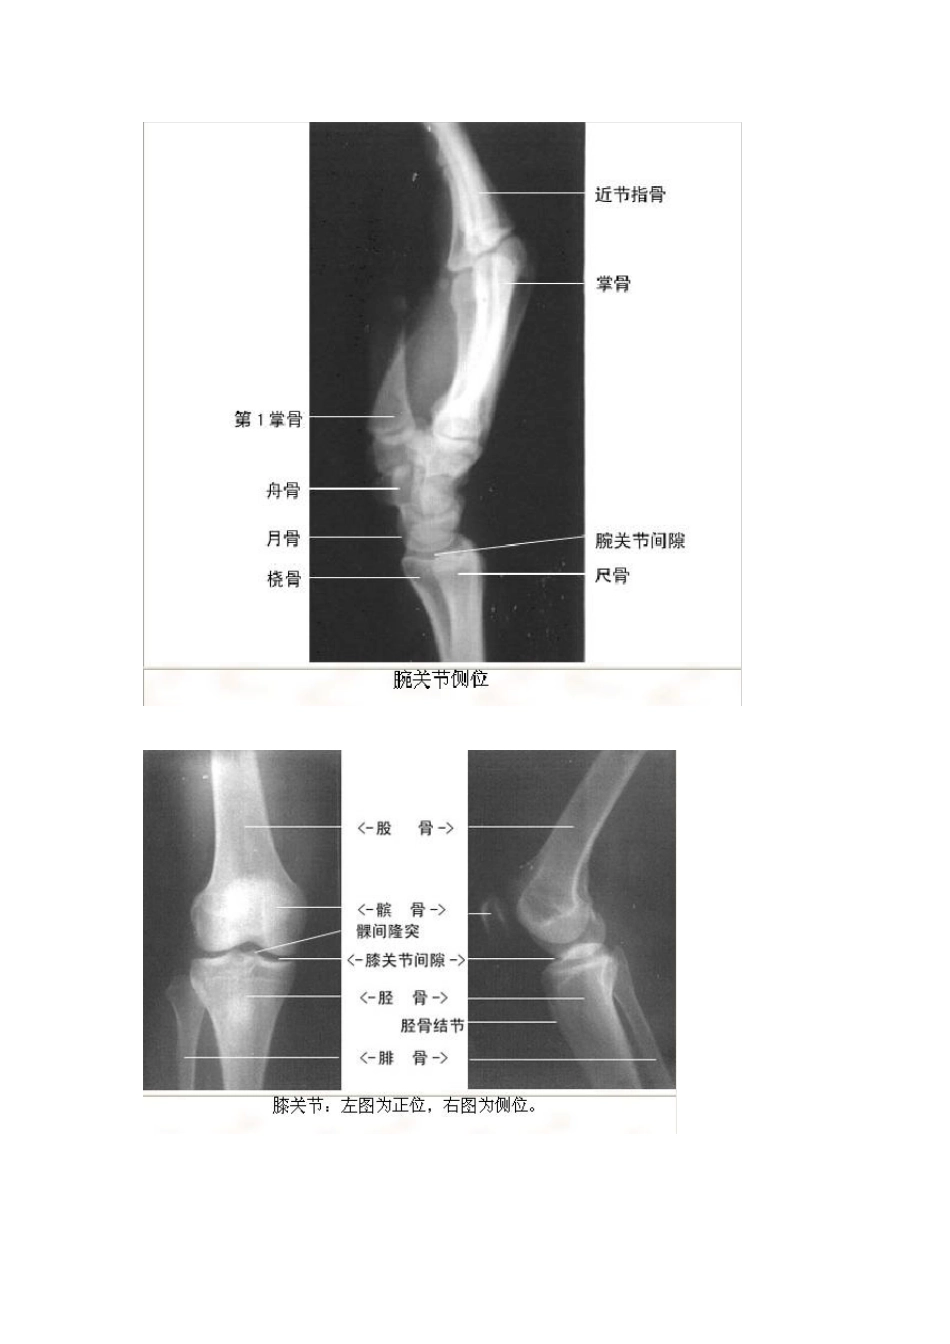

【转】影像看片——X线解剖( 绝版收藏) 转载自: 赵宇泽 转载于:2010-11-23 07:14 | 分类:个人日记 阅读:(2) 评论:(0) 想做一个优秀的医生吗? 那就往下看吧! 知识就是粮食! 胸部X 线片系统读片原理 24个字母(A-X)系统读片法,可以减少漏诊。 胸部X 线片系统读片原理 A(Airway)气道在胸上部,看它是否居中,脊柱是否直线经过,气管有无移位,有无纤维组织牵拉使肺容积缩牵、过度充气及压迫。有无支气管气管巨大症,肺叶开口压迫、狭窄、隆突受压等支气管肺癌征象。 B(Bone)肋骨距是否某侧缩窄,肋骨有无缺损,如第一肋骨上缘缺损,有硬皮病、类风湿性关节炎的可能。第7~ 9肋骨下缘缺损示主动脉狭窄,见于儿童先天心脏病;法乐氏四联症可见左肋下缘缺损。咳嗽所致骨折,可见于6~ 9肋,第7肋腋后线可见叉形肋。鸽胸与先天性房室间隔缺损相关,也见于儿童哮喘症或脊柱侧凸严重时伴通气功能降低者。骨脱钙可见于类固醇治疗患者、老年、肾病、或其他代谢病者。 C(Cor)心脏右缘有两弓,左缘有四弓。右两弓消失见于漏斗胸、右中叶萎缩、肺炎。形状变化或心脏扩大,见于先天性心脏病、心力衰竭。 D(Diaphragm)膈肌右高于左半个肋间隙,一侧高,考虑胸部肿瘤、纤维组织牵拉、膈下脓肿。半侧膈肌升高考虑外伤、中风、颈部感染或肿瘤、肺炎或放射治疗后。右侧可见膈肌伴弯刀征。医 学.教育 网原 。创 E(Esophagus)食管位于气管右,若有空气液面,考虑食管不能松驰或狭窄。 F(Fissures)肺裂将各肺分为各叶,左右各有一斜裂,右侧有横裂,斜裂下端止于膈肌,决不止于前胸壁,有异常时示有病变。 G(Gastric bubble)胃泡在左侧,若在右,考虑内脏转位,胃泡不见,考虑食管不能松驰。胃泡在心右可能为膈疝。 H(Hila)肺门移位示肺部分萎缩、过度充气等,肺门区扩大可能是肺癌转移、肺内感染、免疫疾病或结节病。 I(Interstitium)间质性浸润分两型,间质型看上部心前区,下部可因妇妇女乳房影加重。肺泡型浸润,因肺泡灌注水、脓、血或蛋白质样物质,见于Goodpasture 氏征、肺含铁血黄素沉着症、鳞状上皮脱落间质性肺炎等。观察咳出物对鉴别诊断有用。医学 教。育网 原.创 J(Junction lines)连接线是垂直的,仅见于纵膈,有右脊柱旁、右主动脉旁、右心旁线,左脊柱旁、左主动脉旁、左心旁线,前后连接线等,一般看不见。若看见或突出时,为有块状病推移。 K(Kerley`s lines)克氏线原来只有B 线...